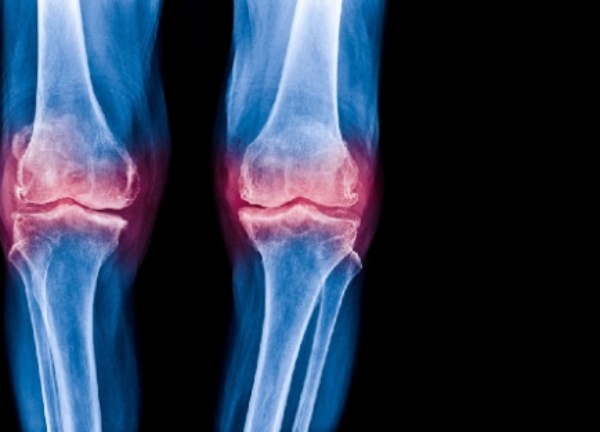

관절염 개선

우리 체내의 뼈를 구성하는 연골이 있다. 그 연골은 나이가 먹음에 따라 점차적으로 감소 하는데, 그 감소하는 역할인 단백분해효소를 직접적으로 감소함으로 관절건강 유지를 하는데 보스웰리아 효능이 발휘한다고 한다.

한 연구자료를 예로 들면, 실제 미국에서 관절염 개선에 대한 내성 연구를 진행하였는데, 보스웰리아를 먹은 그룹은 무릎 통증이 아주 많이 감소했고, 움직임 개선, 관절 붓기 감소와 같은 효과가 나타났다고 한다.

이처럼 관절염 연구 결과에 따르면, 보스웰리아 추출물은 관절염에 효능이 있음을 보여준다. 통증과 부기를 완화하는 등 관절염 개선 효과가 상당하다고 하여, 많은 이들이 이미 찾기 시작하는 제품중 하나이다. 관절염은 특별한 요인이 없더라도 노화 과정에서 누구나 겪게 되는 질병이기 때문에 미리 준비해두고, 관절염에 좋은 성분이 풍부하게 들어 있는 보스웰리아 식품으로 그 증상을 완화할 수 있을 것이다.